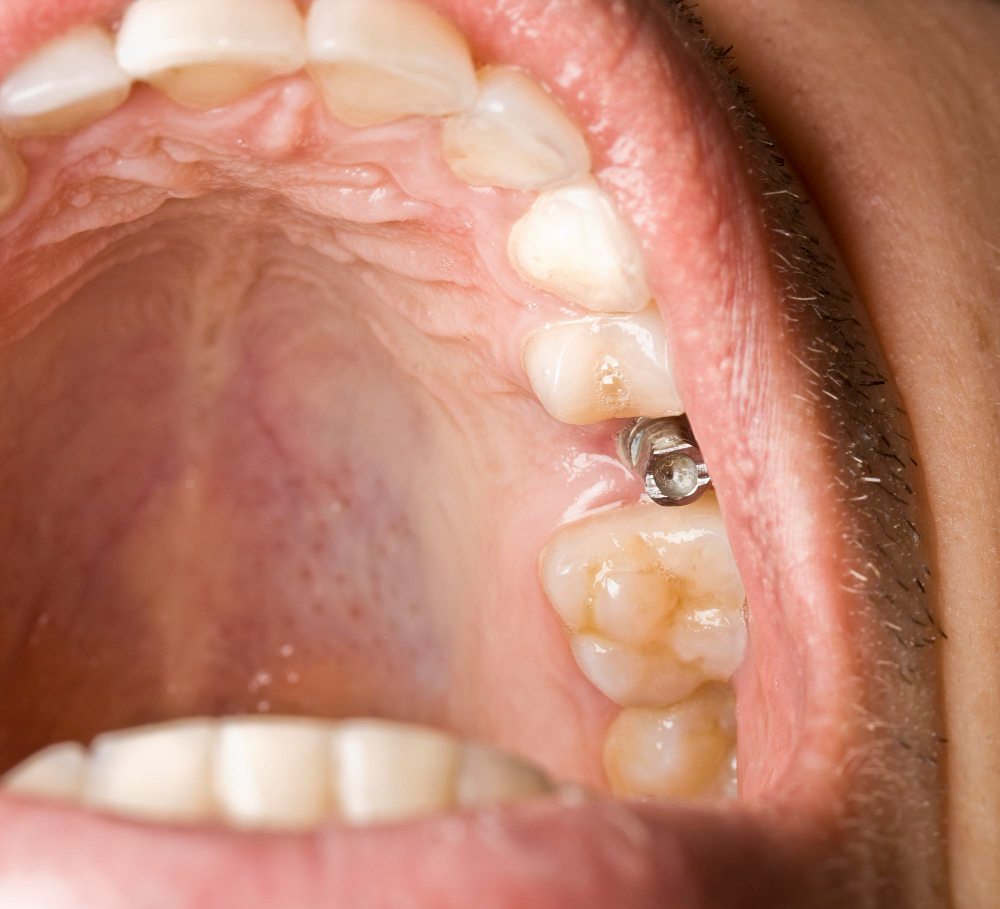

Çocuklarda diş ağrısı genellikle çürük, diş eti enfeksiyonu veya travma gibi nedenlerden kaynaklanır. Ağrının sebebini anlamak ve doğru müdahalede bulunmak önemlidir.

Diş Çürükleri: Dişte hassasiyet ve zonklama şeklinde ağrı yapabilir.

Diş Eti Problemleri: Şişlik ve kızarıklıkla kendini gösterir.

Diş Travmaları: Düşme veya darbe sonucu oluşan çatlak veya kırıklar ağrıya neden olabilir.